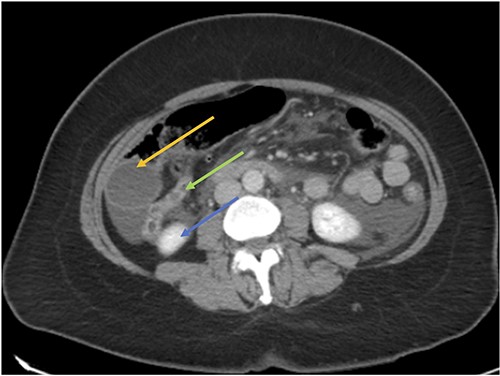

Acute cholecystitis (yellow arrow) with the high riding cecum (green arrow) and subhepatic appendix (blue arrow).

CT axial view showing the appendix (green arrow) inferior to the gallbladder (orange arrow) and superior to the right kidney (blue arrow).